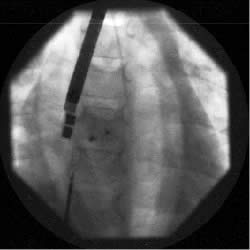

La procedura di impianto viene eseguita in anestesia generale con intubazione del paziente. Un ruolo essenziale, in tutte le fasi della procedura, è svolto dall’ecocardiografia transesofagea. Essa detta le indicazioni alla “fattibilità” (diametro del difetto, misura dei rims settali, ritorni venosi, anatomia atriale), guida l’operatore nel posizionamento della protesi a cavallo del difetto e nel successivo rilascio della stessa, permette una immediata valutazione del risultato (“tenuta” del device dopo rilascio, shunt residuo) (Figure 1, 3, 4). Dall’ottimale utilizzo e dall’esatta interpretazione dei dati forniti dall’ecocardiografia transesofagea dipende in larga parte la riuscita della procedura. Alcuni Autori riportano l’impiego di altri sistemi di monitoraggio durante la procedura quale ad esempio l’ecocardiografia intracavitaria (49). Quest’ultima consentirebbe di evitare l’uso dell’ecocardiografia transesofagea e quindi la necessità dell’intubazione.

Tre pazienti presentavano un difetto singolo associato ad aneurisma del setto interatriale e tre pazienti avevano difetti multipli. In una paziente di 14 anni veniva evidenziato all’ecocardiografia transesofagea e confermato angiograficamente il ritorno venoso anomalo della vena polmonare superiore destra in vena cava superiore. La chiusura del difetto interatriale veniva praticata nel corso di un successivo cateterismo cardiaco dopo aver richiesto ed ottenuto un nuovo consenso dai genitori.

Il diametro del difetto, calcolato con “stretched diameter”, variava da 9 a 32 mm (media 17.6 mm) e la misura dei dispositivi utilizzati da 10 a 34 mm (media 18 mm). Tutti i difetti sono stati chiusi utilizzando un singolo device ad eccezione di una paziente con difetti multipli in cui sono stati utilizzati due device di diverso diametro.